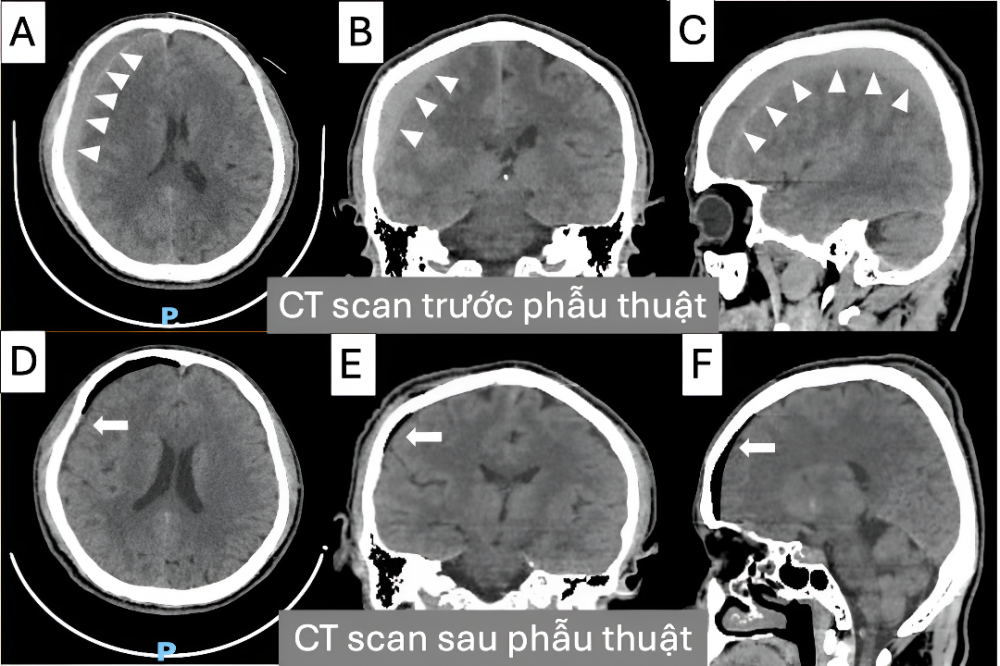

Kết quả CT sọ não cho thấy máu tụ dưới màng cứng vùng trán - đỉnh phải, giai đoạn bán cấp, dày khoảng 12 mm, gây đè đẩy đường giữa sang trái #6mm, đè đẩy nhu mô não. Bệnh nhân được chỉ định phẫu thuật khoan sọ dẫn lưu máu tụ (burr-hole evacuation).

Hình 2. CT scan sọ não trước phẫu thuật (A, B, C) và sau phẫu thuật (D,E,F) lấy máu tụ dưới màn cứng mạn tính với phẫu thuật khoan sọ lấy máu tụ và đặt dẫn lưu kín

(burr-hole drainage) ở bệnh nhân lớn tuổi.